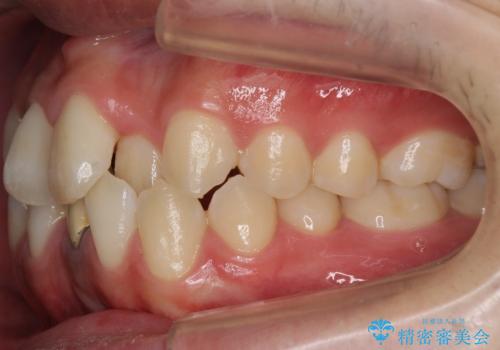

- 前歯のガタガタを主訴に来院。

下の前歯は一本保険治療での被せ物になっており、変色していました。

・神経のない下の前歯を残す

・神経のない歯を抜いてしまって、天然歯で閉じる

のプランを提案し、神経のない前歯を抜く選択をされました。

下の前歯が3本になり奇数になることで、上下の真ん中は一致しませんが、そこまで目立たないと思います。

残りは全て天然歯になり、人工物の心配をしなくて済むようになりました。